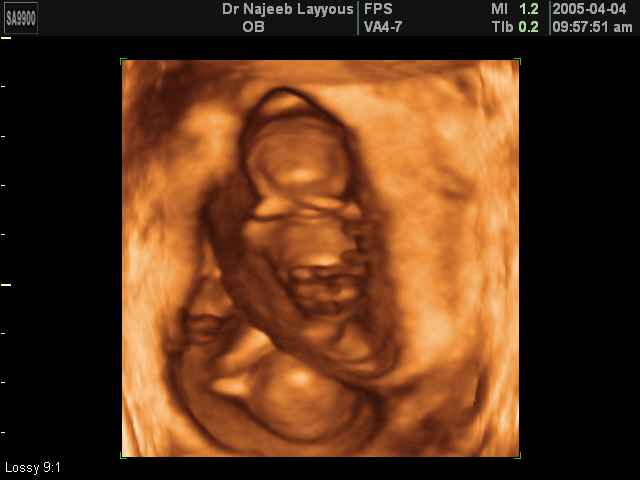

- 3D Photos échographie de grossesse multiple